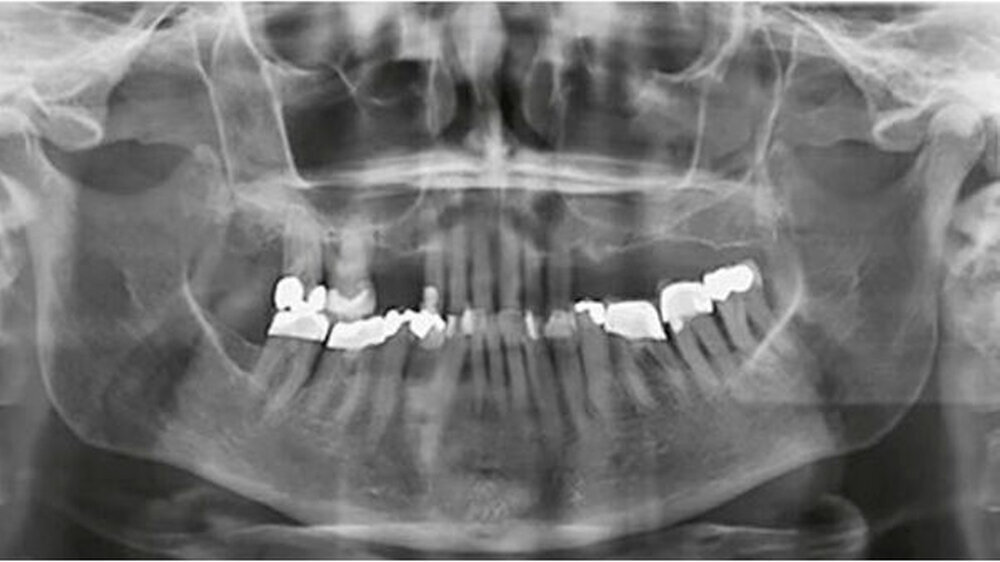

Als sich die Patientin in einer allgemeinmedizinisch stabilen Situation befand, erfolgte eine Vorstellung mit Verdacht auf einen oralen Fokus in der Klinik für Mund-, Kiefer- und Gesichtschirurgie sowie in der Klinik für Zahnerhaltungskunde & Parodontologie des Universitätsklinikums Freiburg. Die Befundung der Patientin zeigte eine schwere chronische generalisierte Parodontitis mit Sondierungstiefen bis zu 7 Millimeter und einen generalisierten horizontalen Knochenabbau (Abb. 3 und 4). Dabei ist zu beachten, dass der Parodontalstatus einen Zustand nach Scaling und Wurzelglätten sowie Antibiose und antiinflammatorischer Therapie darstellte. Um eine rezidivierende Infektion zu vermeiden, wurde eine strenge Extraktionsplanung vorgenommen, basierend auf der Prognoseeinschätzung von Nunn et al. (2012).